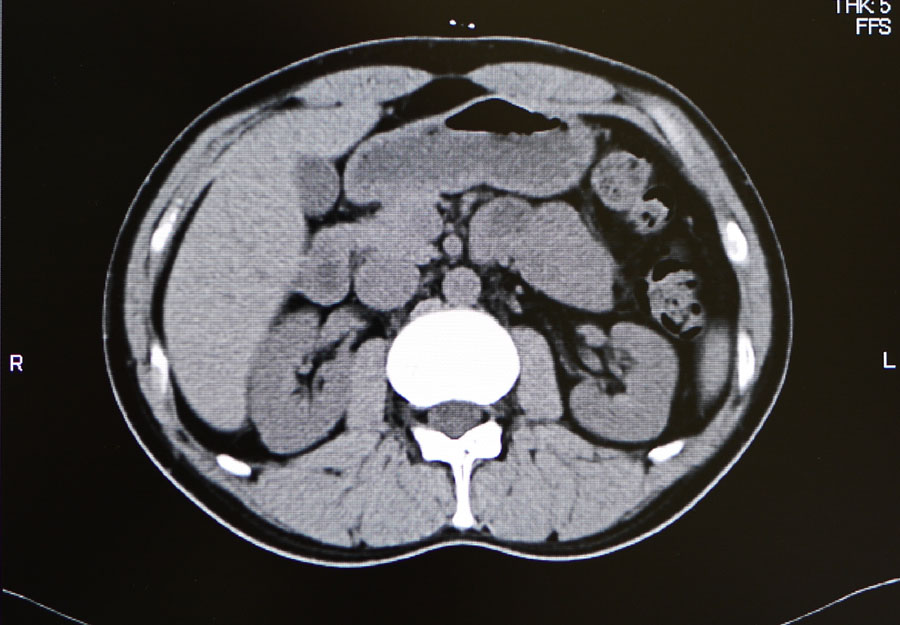

【単純CT】

問題なし! 【腫瘍マーカー】 HCGβ:<0.1 問題なし! 次は9月!

問題なし 【腫瘍マーカー】 HCGβ:<0.1 問題なし 【中性脂肪】 219→137 基準内(38-193)に入った 今回、検査画像をデータでもらってきた。 後腹膜の転移した箇所の前後4枚を2003年から2010年まで並べてみた。 http://gomatsushita.gozaru.jp/ct/album/index.html 2006/7/18の画像を見ると腫瘍がハッキリ見える。 BEP2クール後の9/27の画像では明らかに縮小もしくは消滅。